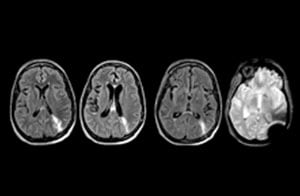

When neurological emergencies require diagnostic imaging, common practice in the ED has been to perform CT rather than MRI, even when MRI could potentially produce more informative diagnostic images of spinal cord damage, disc protrusions, soft tissue injuries, and stroke pre-cursors. [1,2] The main reason is that timing is essential in emergency cases, and CT is generally faster than MRI. The St. Joseph’s Hospital and Medical Center is now challenging this paradigm by offering rapid MRI scans within its Neurologic ED and seeing that it helps them make a richer diagnosis.

To minimize the time taken to perform scans, rapid MRI examination protocols (ExamCards) were developed, shortening the total scanning time to even less than 10 minutes in some exams. Techniques like mDIXON (modified DIXON) are used for robust capturing of fat-free MRI images in a hectic ED environment.

“One of the most important decisions an ED physician has to make is to admit or discharge their patient. So a physician who is better informed by an MRI exam can make this decision with more confidence. By converting to a test that has a far better potential to identify issues, physicians get a better and more certain diagnosis."

"In my experience a negative MRI, because it is so sensitive to abnormality, far exceeds the value of a negative CT. A negative MRI can allow physicians to be more confident about making discharge decisions, potentially reducing the number of admissions in cases of doubt, and offering cost savings for the institute."

“Our results show that a dedicated MRI in the ED can be effectively implemented; patient turnaround times with MRI were on par with CT. Interestingly, even though the MRI exam protocols were shortened, this robust yet rapid scanning still yielded good quality images, further improving our workflow and almost eliminating the need for repeat scans or follow-up scans. So, we’re heading towards first time right imaging,” says Dr. Karis.